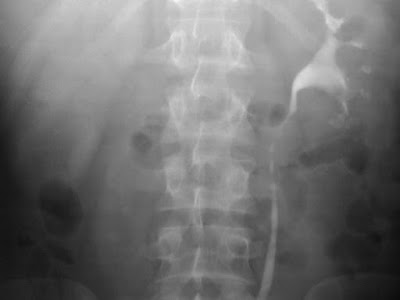

Obstructive uropathy

Persistant delayed nephrogram of the right kidney in a UVJ calculus.